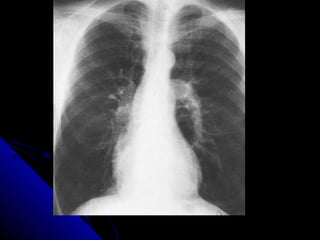

PPlleeuurraall eeffffuussiioonn

AA pplleeuurraall eeffffuussiioonn iiss ssiimmppllyy aa ccoolllleeccttiioonn ooff fflluuiidd

bbeettwweeeenn tthhee vviisscceerraall pplleeuurraa aanndd tthhee ppaarriieettaall

pplleeuurraa.. TThhiiss fflluuiidd ccoolllleeccttiioonn mmaayy bbee sseerroouuss

((pplleeuurraall eeffffuussiioonn)),, bblloooodd ((hheemmootthhoorraaxx)),, oorr ppuuss

((eemmppyyeemmaa))..

UUpprriigghhtt PPAA ffiillmm:: sshhaappee,, ddiissttrriibbuuttiioonn..

LLaatteerraall ffiillmm:: ppoosstteerriioorr CCPP rreecceessss..

SSuuppiinnee ffiillmm..

LLaatteerraall ddooccuubbiittuuss ffiillmm..